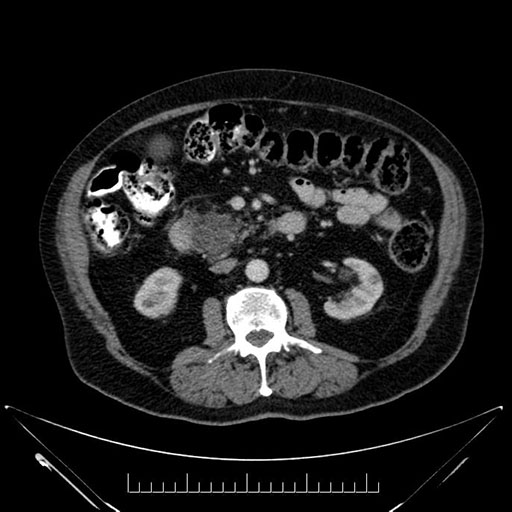

Whipple (pancreaticoduodenectomy) [case 7]

Imaging Analysis

Look through the patient's CT scan to identify any areas of concern for the necessary procedure.

Axial - stented